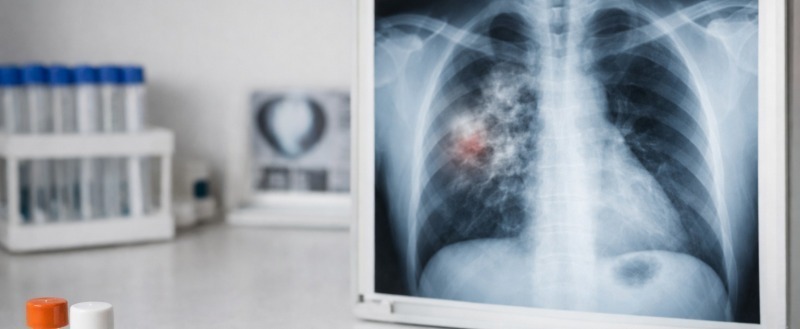

- Флюорография (ФЛГ) – способ, позволяющий выявлять начальные формы туберкулеза, а также другие заболевания легких, на ранней стадии. Своевременно обнаруженный туберкулез полностью излечим. Но чем больше запущено заболевание, тем сложнее с ним справиться. Именно поэтому необходимо проходить флюорографические обследования не реже одного раза в 1-2 года.

В чем разница между ФЛГ и рентгеном, что предпочтительнее для постановки диагноза?

- Основной задачей ФЛГ является профилактическое обследование, ее главные особенности –скорость и общедоступность. У нас на отделении лучевой диагностики установлены флюорографические и рентгенодиагностические аппараты разных производителей, в том числе отечественные «Электрон». Могу сказать, что флюорографическое изображение, получаемое на современных цифровых аппаратах, по качеству практически не уступает рентгенограмме. Рентгенография относится к уточняющей диагностике: она используется, когда заболевание уже заподозрено или выявлено при скрининге. Рентгенография информативнее ФЛГ, так как дает более четкие и детализированные изображения и широкие возможности постобработки.